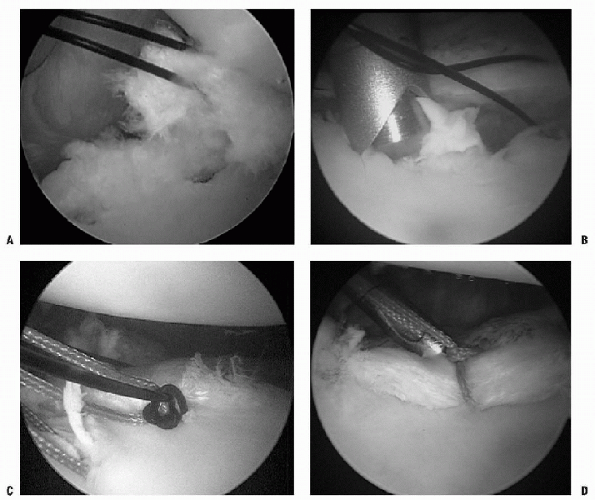

The anchor-first technique involves

shuttling the suture limb second (Fig. 17-14).

Figure 17-14 A: Example of an anchor first shuttling technique with a tissue penetrator inferior to the anchor. B: Nonabsorbable suture shuttled through the inferior labrum and inferior glenohumeral ligament complex.

Figure 17-15 A: Arthroscopic view of suture-first technique. Zero PDS placed inferiorly and traction applied. B: Anchor placement more cephalic to suture, so that with eventual knot tying, the labrum and capsule are shifted superiorly. C: Nonabsorbable suture being shuttled with zero PDS. D: Knot-tying.

The suture-first technique involves

shift, followed by placement of the anchor (Fig. 17-15). A suture-passing device is placed through the anterior-inferior

P.227cannula. The capsular tissue is imbricated inferior to what would be

the 5 o’clock anchor position, thus enabling the tissue from

anterior-inferior glenohumeral ligament to be shifted superiorly. The

passing suture is passed through the tissue and shuttled through the

anterior-superior portal. The suture-passing device is removed, and the

suture limb that is in the anterior-inferior portal is switched to the

anterior-superior portal. Tension is placed on this suture to observe

the amount of shift that can be accomplished by placement of the anchor

at the appropriate position. -

If it is determined that this suture is not inferior enough, a second suture can be placed.

-

When an appropriate amount of tissue

tension is established, the anchor is placed through the

anterior-inferior portal and onto the glenoid rim. As was described

previously, once the anchor is placed, the two limbs of the suture are

separated—one through the anterior-superior cannula and the other limb

is shuttled through the tissue. -

The same steps are repeated two or three times, depending on the repair quality and amount of injury (Fig. 17-16).